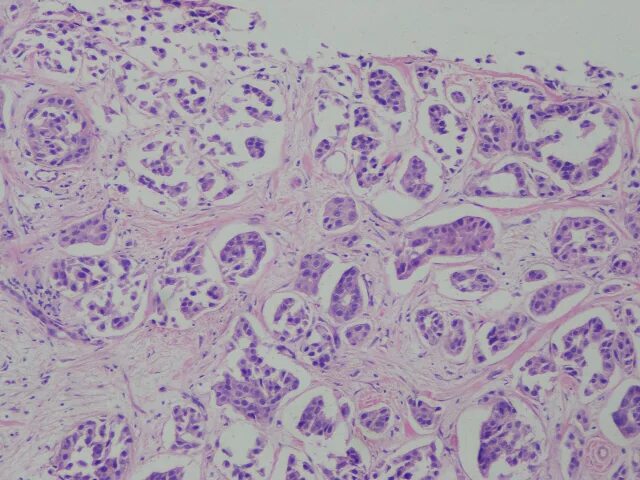

Фиброаденома гистология